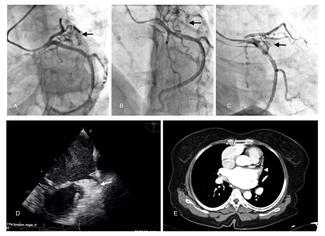

Felix Maverick Uy, MD1; Amar Vaswani, MBBS2; Kiang Hiong Tay, MBBS3,4; Soo Teik Lim, MBBS, MRCP2,4; Jonathan Yap, MBBS, MRCP, MPH2,4

A 73-year-old female presented with exertional dyspnea and was found to have a coronary artery to pulmonary artery fistula with 2 sequential giant aneurysms.